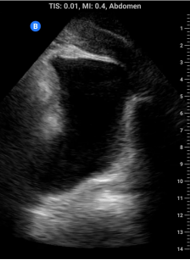

The normal renal collecting system should appear echo bright. The presence of anaechoic space is suggestive of hydronephrosis. Shown below on the left is a normal kidney while on the right is an example of moderate hydronpehrosis showing dilation of the renal pelvis and major calyces.